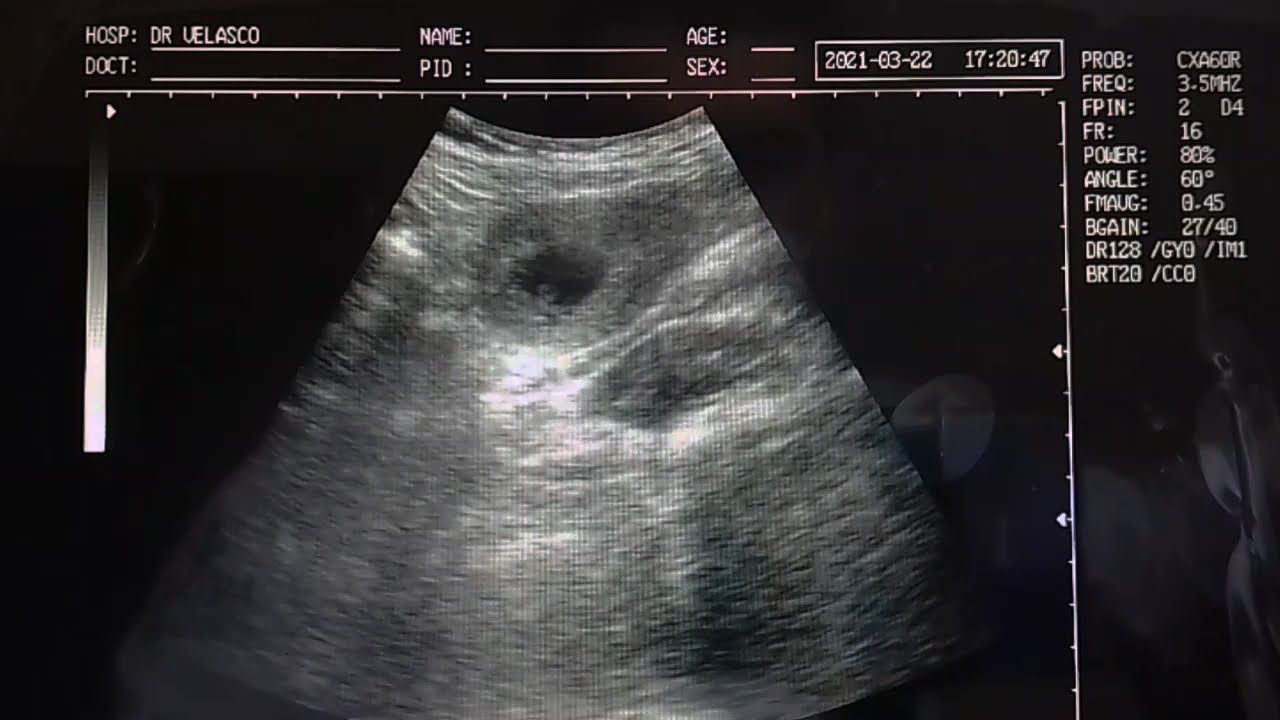

La velocidad de sus latidos es normal para esta etapa gestacional. El corazón del embrión en la semana seis de embarazo está formándose y ya tiene 2 vasos sanguíneos. El corazón de un feto late muy rápido, no debes asustarte cuando te realizen la ecografía y escuches un latido a 150 pulsaciones porque es normal. De hecho a través de una ecografía podras ver una forma como de judía latiendo intermitentemente. El tamaño del embrión de 6 semanas de gestación es de 4 a 6 milímetros, siendo equivalente al tamaño de una semilla de granada. Cambios en el cuerpo de la mujer en la sexta semana de embarazo, los niveles de hormonas están cada vez más altos y pueden acentuarse los síntomas de cansancio, somnolencia, náuseas matinales, mamas adoloridas o pesadas y sensación de. A las 6 semanas de embarazo, el bebé tiene el tamaño de un guisante dulce. El embrión promedio en la semana seis es aproximadamente 0. 25 pulgadas y doblará en tamaño otra vez la semana próxima. ¿6 semanas de embarazo, son cuántos meses?

Reseñas Embarazo de 6 semanas 2D actualizar

Artículos EMBRIÓN DE 6 SEMANAS DE GESTACIÓN POR ECOGRAFÍA tendencias

Últimas Ecografia 2D gestacion de 6 semanas medidas embrion CRL Último

Últimas Ecografía 6 semanas de embarazo ¿ se escucha el corazón ¿ cuanto mide el embrión 💖 más